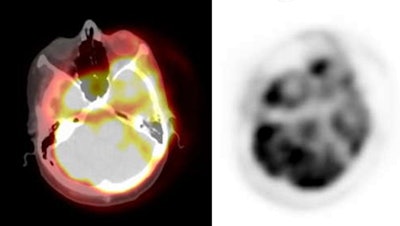

| PET/CT exam: The images below are from a PET/CT exam. The patient moved between the acquisition of the CT study and the PET exam- hence- there is misalignment of the two exams. |